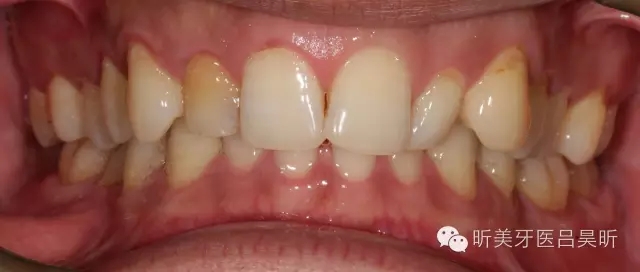

術(shù)前口內(nèi)檢查,可見(jiàn)牙槽骨寬度良好,角化齦量適中